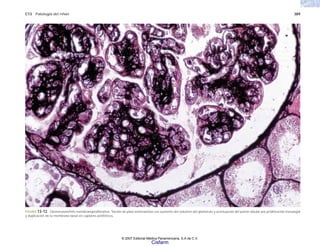

FIGURA 2-9. Perforaciones circulares en la membrana de un eritrocito de un paciente con hemoglobinuria paroxística, después de reaccionar con anticuerpo y complemento. (Tomado de

Dourmashkin RR, Rosse WF: Am J Med 41:699, 1966.)